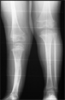

Pre

Op

Deformed and shortened leg in a 3 years old child